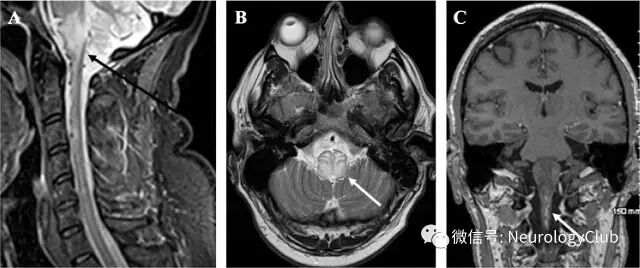

除MRI上证实的广泛水肿外,增强后可见匐行性扩张的前髓静脉强化,提示瘘所致的动脉化可能。血管造影证实起源于右后脑膜中动脉分支的小脑幕动脉小分支和深部小脑脑桥静脉通路之间瘘点的存在,引起脑干和上脊髓较高的静脉回压,淤血和缺血。

患者的瘘点通过胶栓成功闭塞(图2)。6周后复查MRI可见脑干异常信号明显好转。患者可拔管独立呼吸,运动功能也几乎完全恢复。

(图2:A-B:脑膜中动脉后分支血管造影可见硬脑膜动静脉瘘[箭];C:栓塞术后可见瘘点消失)